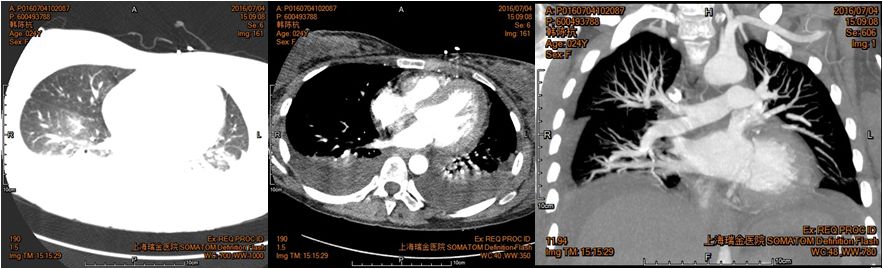

肺动脉CTA:双侧胸腔积液,两下肺膨胀不全伴部分实变;两肺纹理清晰(未见动脉栓塞征象)。